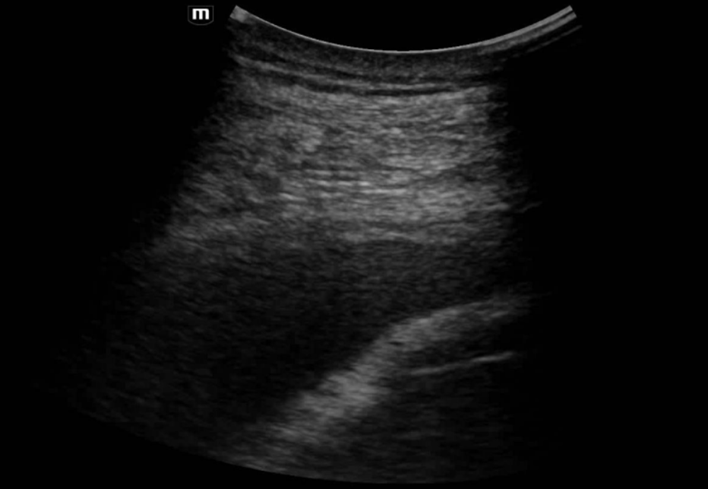

1.ª ecografía: hepatomegalia, distensión de venas suprahepáticas y vesícula biliar de paredes engrosadas.

La exploración convencional fue insuficiente para explicar la disnea y la congestión hepática, lo que motivó la realización de ecografía en Atención Primaria.